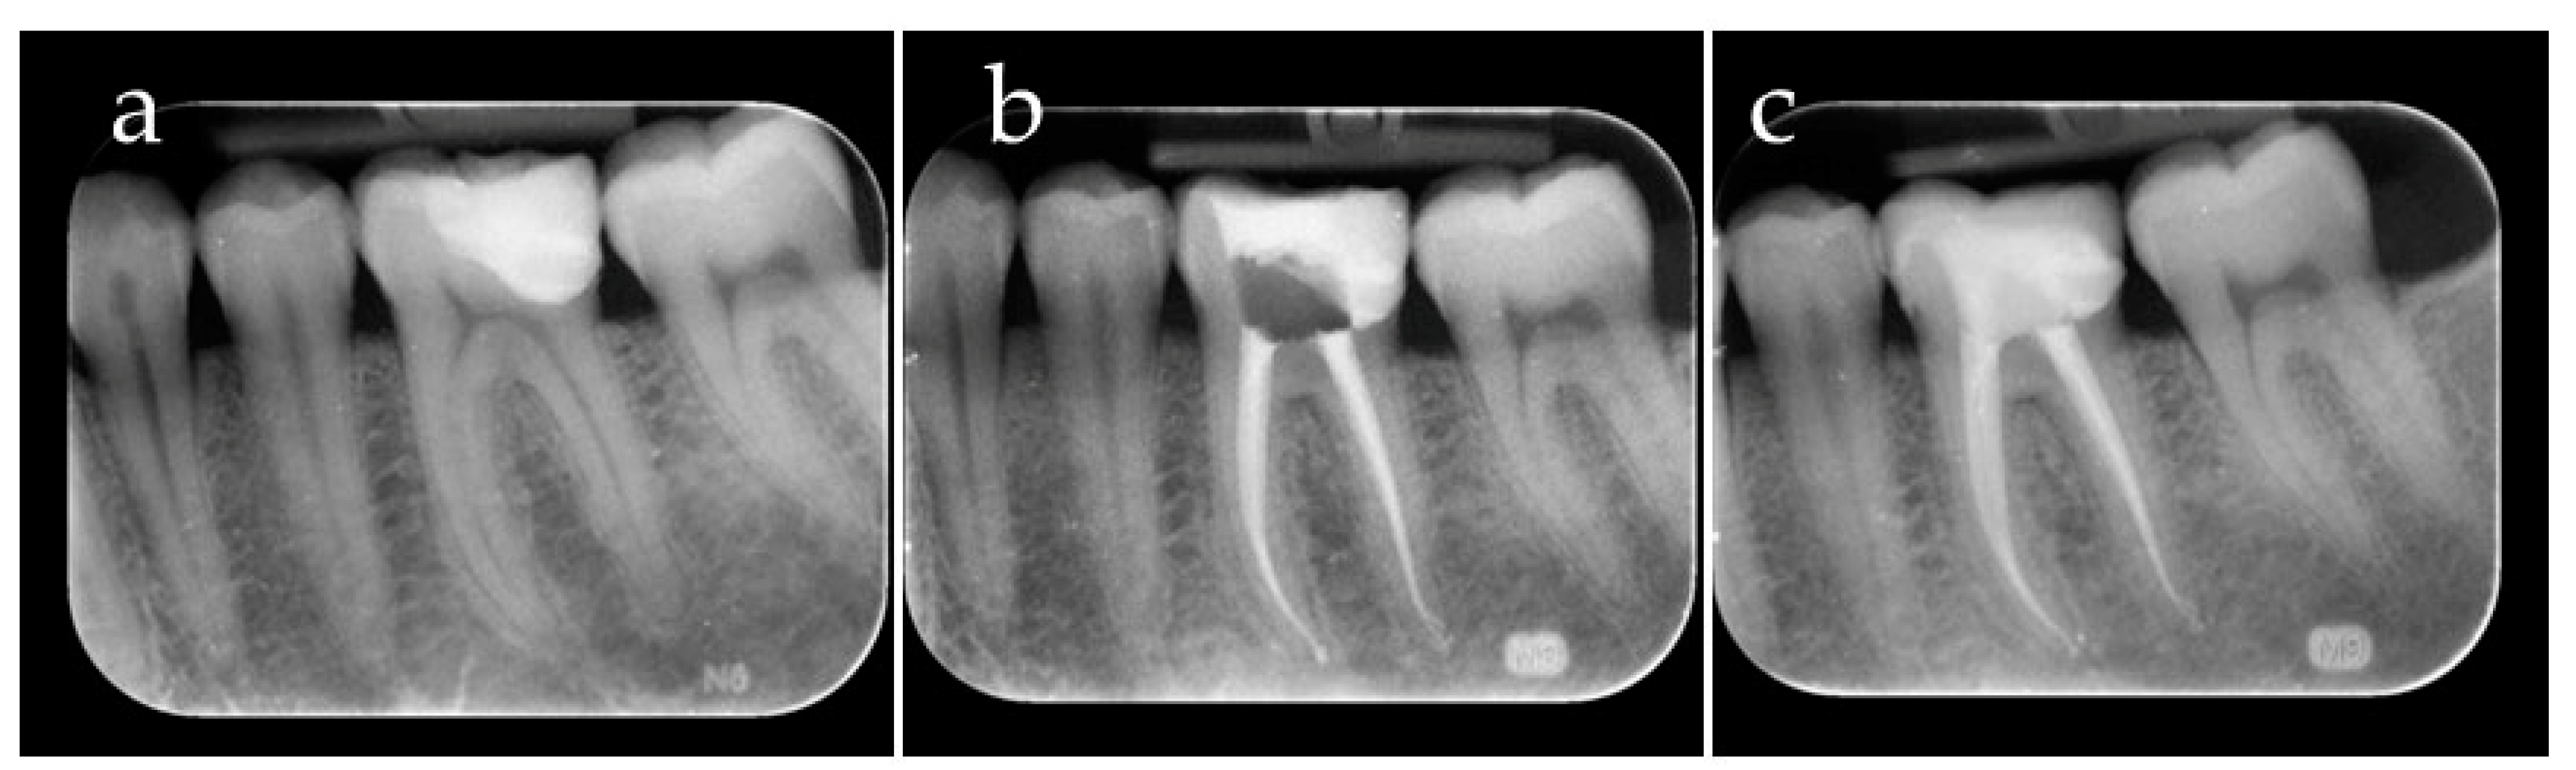

2. Case Report